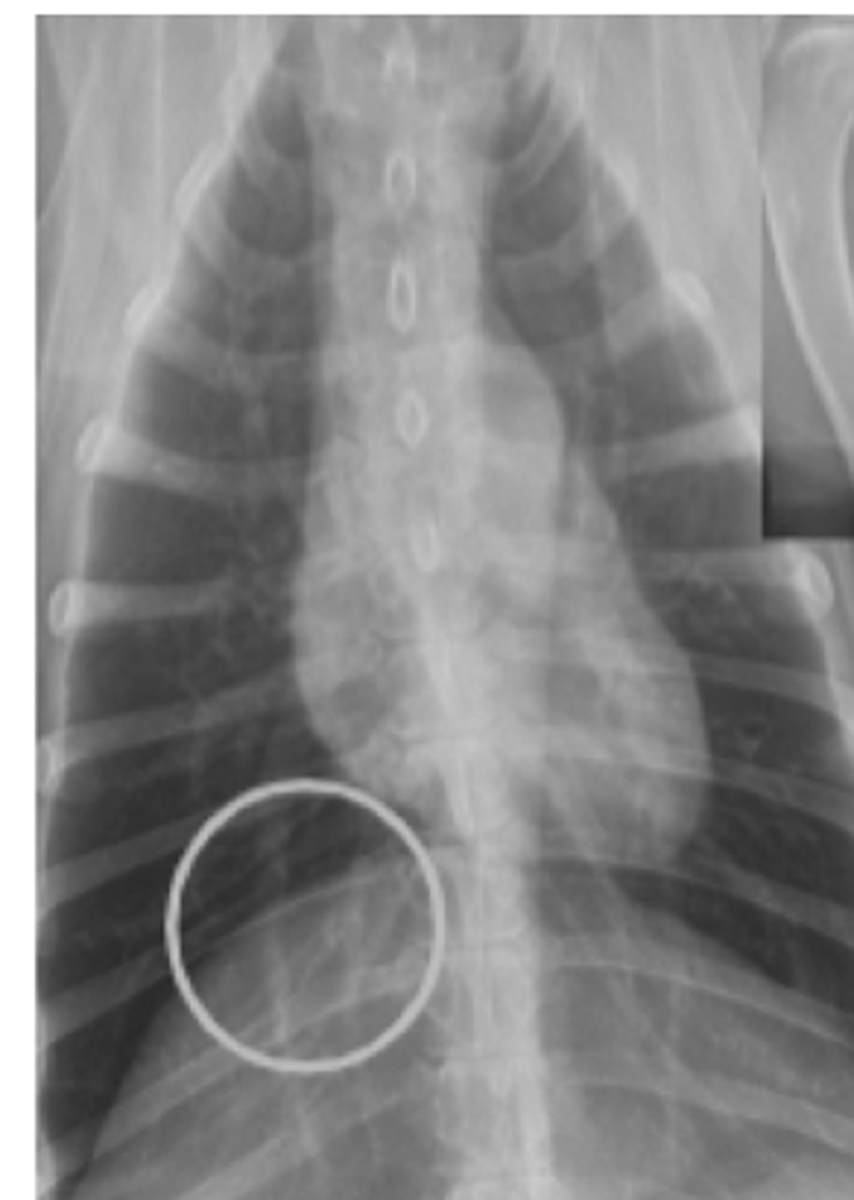

efusión pleural

patología:

efusión abdominal

pneumotorax

patolgía